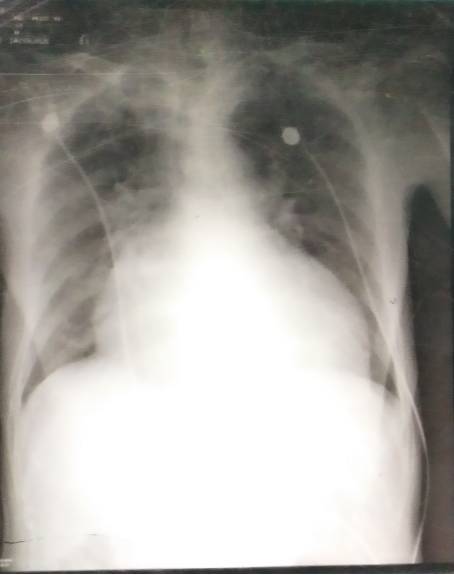

床旁胸片:15-06-13:11:31

扩张型心肌病

全心增大